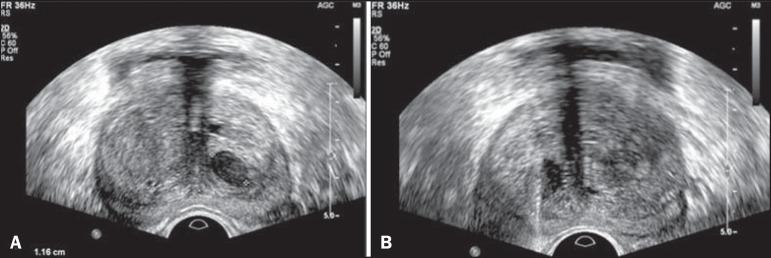

The present study was aimed at evaluating the contribution of transrectal prostate ultrasound in the screening for prostate neoplasias and in the guidance of prostate biopsies.

Prospective study developed over a one-year period. All the patients with indication for prostate biopsy were evaluated. Regardless of PSA values, the patients underwent ultrasound in order to identify suspicious nodules (confirmed by two observers). Sextant biopsy was subsequently performed. In cases of finding suspicious nodules, an additional puncture directed to such nodules was done.

In a total of 155 cases the prevalence of malignancy was of 53%. Suspicious nodules were detected in 34 patients, and 25 where malignant (positive predictive value of 74%). The specificity and sensitivity for suspicious nodules were 88% and 31% respectively. Comparatively with the randomly obtained sextant specimens, the rate of findings of neoplasia was higher in the specimens obtained with puncture directed to the nodule (p = 0.032). No statistically significant difference was observed in the Gleason score for both types of specimens (p = 0.172).

The high positive predictive value and the high rate of findings of neoplasia in specimens of suspicious nodules should be taken into consideration in the future. The authors suggest a biopsy technique similar to the one described in the present study (sextant biopsy plus puncture directed to the suspicious nodule).